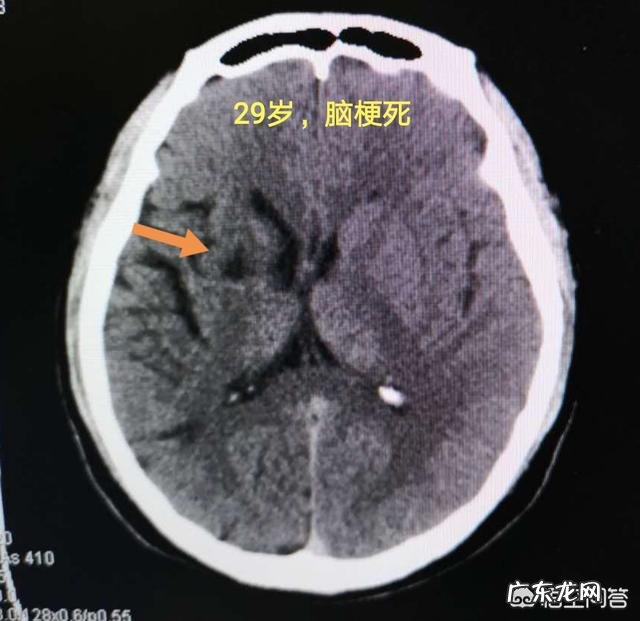

1.男性,29岁,个体经营者也许是今年买卖不好做,过度焦虑,突发嘴角歪斜,左手活动不灵 。

脑CT发现右基底节区脑梗死: